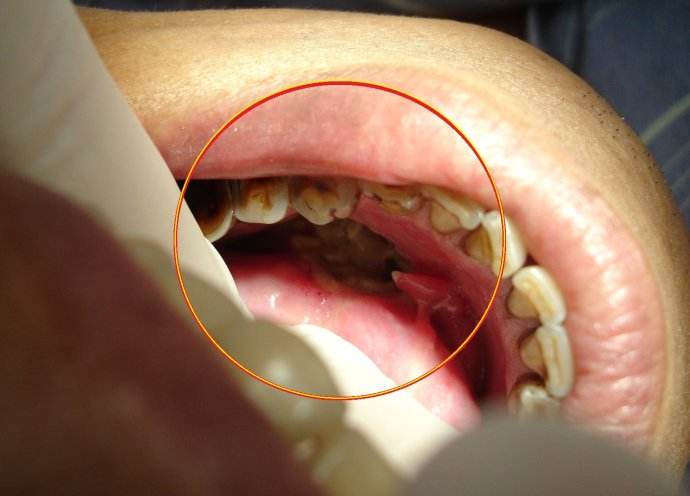

扁桃體惡性腫瘤圖片

扁桃體癌圖 (64)

扁桃體癌圖 (65)